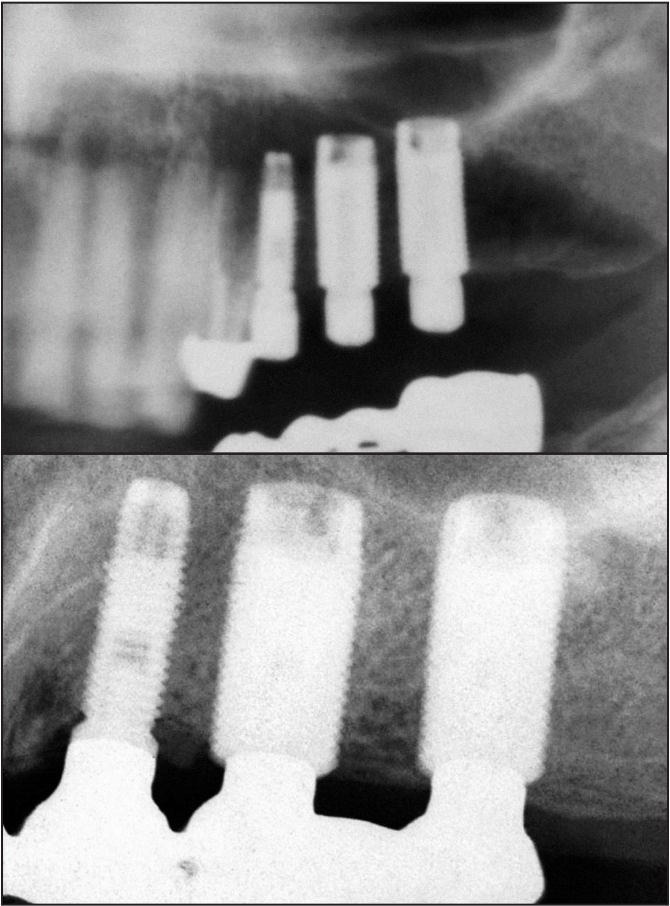

Y de ahí sale esta radiografía que es sin duda la la radiografía más relevante en la implantología contemporánea.

Al alejar el gap, las bacterias y todo el contenido inflamatorio del gap en un sentido horizontal, se observó que había una casi inexistente pérdida de hueso marginal.